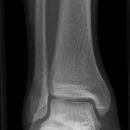

Sprunggelenk seitlich

Malleolus fibularis steht etwa 1cm weiter dorsal und reicht 1,5cm weiter nach kaudal als der mediale Malleolus. Malleolen, abgesehen von ihrer Längendifferenz, exakt übereinander projiziert?

Beurteilungskriterien

Cave: DD Pilon-tibial-Frakturen: metaphysäre, supramalleoläre Frakturen der distalen 4cm der Tibia (meist mit Fibulafraktur kombiniert) -> OSG-Frakturen: Frakturen der Malleolengabel und posterolaterale Tibiakantenabscherungen (Volkmann-Dreieck)

• Malleolen exakt übereinanderprojiziert?

• Gelenkspaltweite in der seitlichen Aufnahme gleichmäßig weit?

• Weichteilschwellung ventral des Gelenkspaltes?

• Gelenkstellung des Talus in der Malleolengabel

• Target areas häufiger subtiler Frakturen:

• Kontur der Malleolen und Malleolarspitzen

• posterolaterale Tibiakantenabscherungen (Volkmann-Dreieck)

• Kanten der Trochlea tali (Flake-Frakturen bei bis zu 7% der OSG-Distorsionen!)

• Talushals, Processus posterior tali

• Cave : akzessorische Knochen (Os trigonum, Os supratalare, Os supranaviculare, Os tibiale externum)